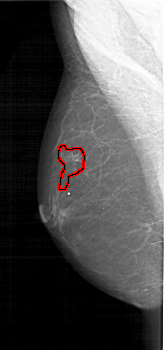

FILE: A_1178_1.LEFT_MLO.OVERLAY

TOTAL_ABNORMALITIES 1

ABNORMALITY 1

LESION_TYPE CALCIFICATION TYPE FINE_LINEAR_BRANCHING DISTRIBUTION SEGMENTAL

ASSESSMENT 5

SUBTLETY 5

PATHOLOGY MALIGNANT

TOTAL_OUTLINES 1

BOUNDARY